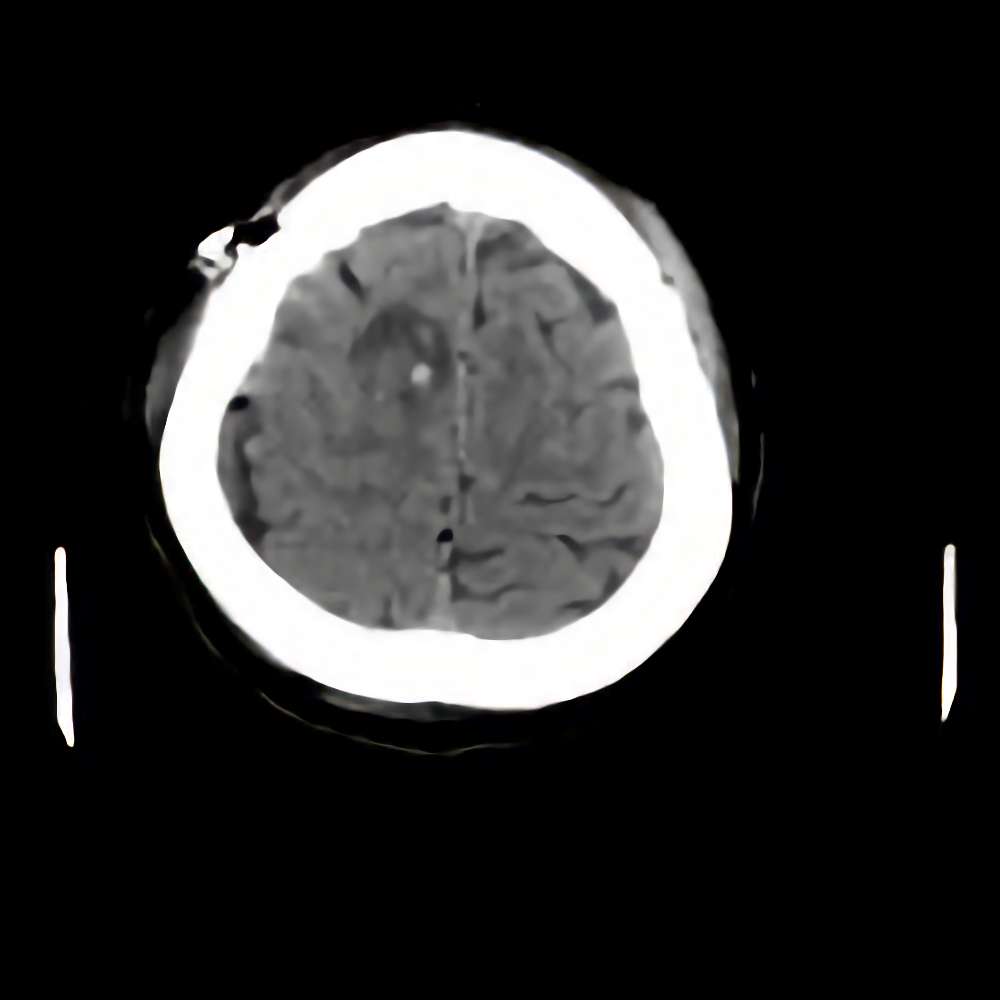

症例 '16年4月

No.

※ 画像をクリックすると拡大表示します。症例No.は平成29年から起算しています。

年_番号

手術年月

患者年齢

’16_42

'16年4月

40代

病名

術式

備考

髄膜腫

(円蓋部)

断層撮影

手術前

1

手術前2

手術後